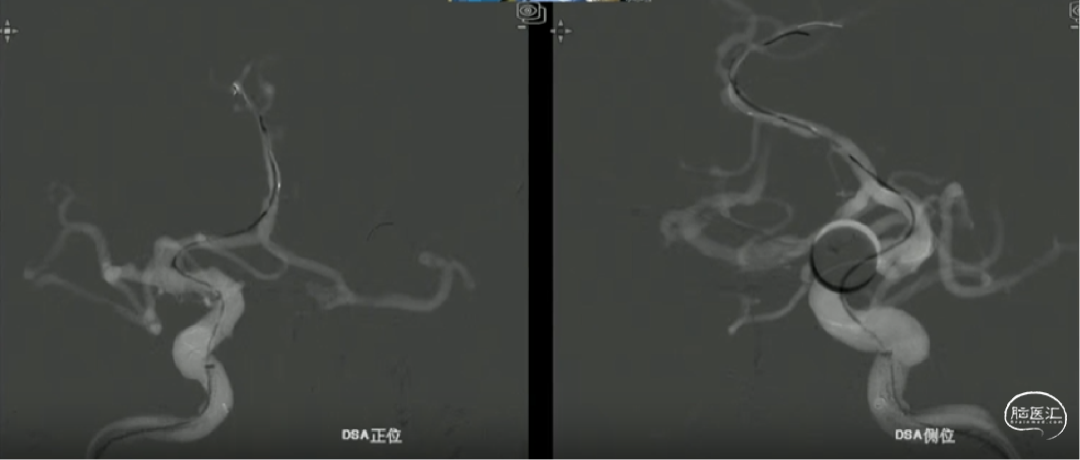

术前影像

· 患者三型弓,奇大脑前A3段动脉瘤,形态极不规则,血管入路极其迂曲

· 从大脑前动脉瘤起始段,有广泛伴有动脉粥样硬化的斑块

· 病变远端处于奇大脑前动脉双分叉位置,远端支架可着陆的空间较短,远端血管较细,且伴随斑块